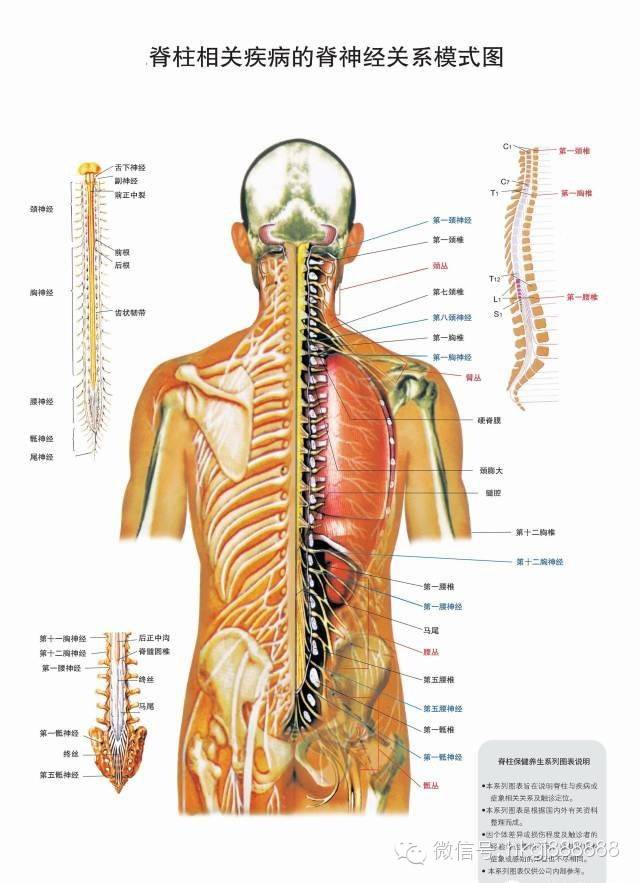

人体骨骼结构示意图 360图片